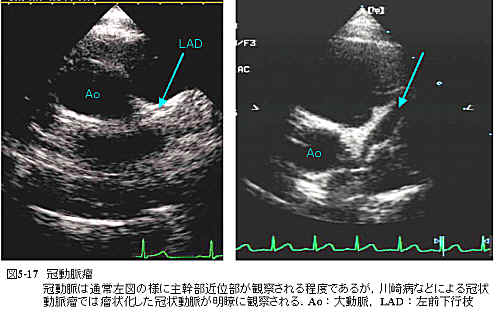

b)冠動脈瘤

図5-17は川崎病既往患者において左前下行枝に冠動脈瘤を呈した症例である.通常冠動脈は主幹部近位部がかろうじて描出されるのみであるが冠動脈瘤症例では瘤状冠動脈が明瞭に描出されることも多く,症例によっては瘤内血栓なども描出される.